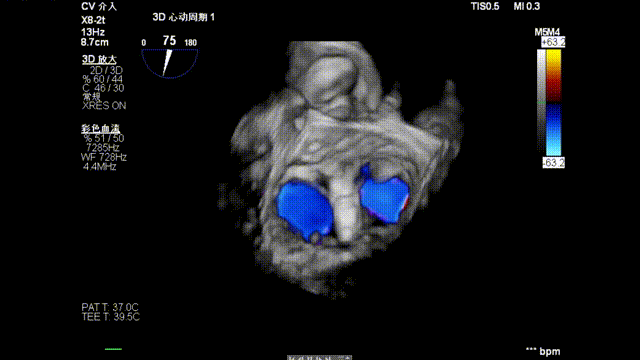

全麻后,二尖瓣夹合器系统在心前区的肋间切开3-4CM小切口,暴露心脏的心尖位置,送系统送入左心房,顺利到达病变二尖瓣区域。在经食道超声辅助下,术者通过反复评估二尖瓣反流位置、抓捕位置、反流程度,首先在2偏3区位置处于二尖瓣闭合线垂直进行巧妙夹合。在2区靠近3区位置处植入了1枚ValveClamp®MVC-IIf夹,最终评估评估反流降至轻度,平均跨瓣压差降至2mmHg,手术取得圆满成功。

术中超声(关键步骤)

术后超声

最终在A3P2位置夹合,前叶夹合量10mm,后叶夹合量8mm,剩余瓣口面积3.45cm²,平均跨瓣压差2mmHg,反流基本消除。